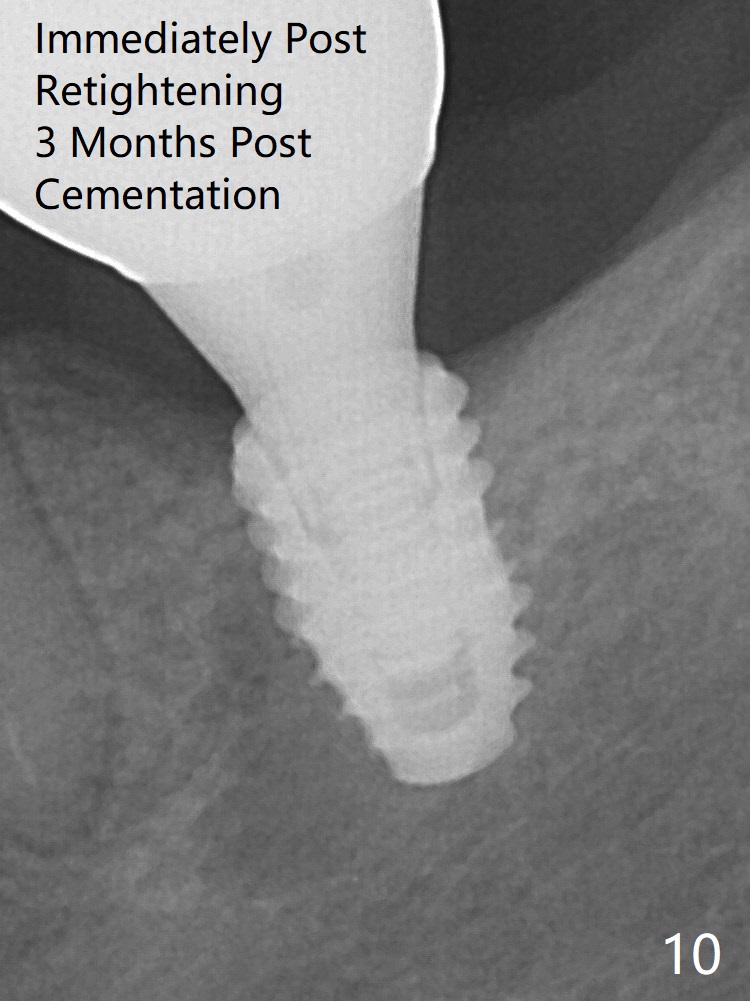

Two months later the patient returns for crown recementation. When the abutment is reseated with the repaired crown, the seating is incomplete (Fig.15). The abutment is completely seated when it is turned free hand with the flat surface of the abutment faces distal (Fig.16 D). The screw is torqued 20 Ncm before reimpression.